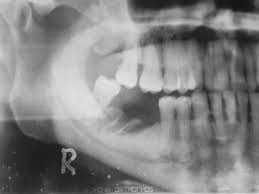

En este  estudio retrospectivo multicéntrico de base poblacional, se encontró que la incidencia de osteonecrosis de mandíbula relacionada con medicamentos (ONMRM)  en pacientes con cáncer de mama con metástasis óseas era considerablemente mayor, especialmente en pacientes que recibían denosumab, en comparación con los datos disponibles en la literatura. Además, las pacientes tratados con denosumab desarrollaron ONMRM significativamente antes. J Clin Oncol. 20 de agosto de 2024

Osteonecrosis de la mandíbula relacionada con la medicación: análisis de la gama de fármacos implicados de la base de datos australiana de notificaciones de eventos adversos

Este estudio contribuye a la escasa pero creciente literatura que asocia un número creciente de fármacos con osteonecrosis de la mandíbula relacionada con la medicación (ONMRM)  y subraya la importancia de considerar todos los fármacos posibles que elevan el riesgo de ONMRM de un paciente. Br J Clin Pharmacol, junio de 2021